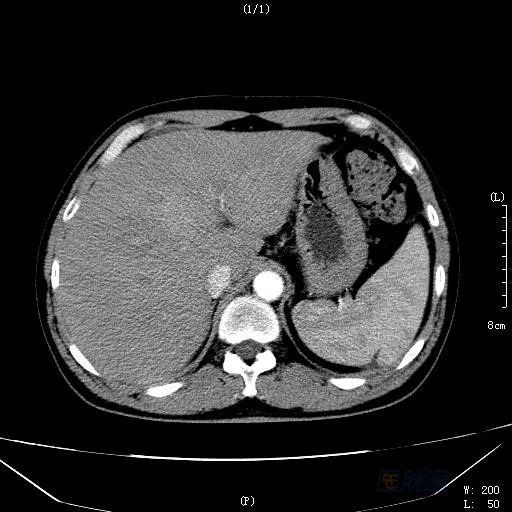

图2 治疗一个月后CT门静脉期扫描

之后,患者电话笔者申请会诊,赴约。仔细阅读病例病史,发现患者并无既往肝病史,乙肝两对半、丙肝等检查无阳性结果,无饮酒等嗜好;患者虽似乎有肝衰竭的症状表现,但凝血指标基本正常,经过保肝治疗,病情也明显好转。阅读CT、MRI发现:肝左内叶见一高密度影,但三期无明显变化,肝脏体积偏大,呈不均质改变,MRI提示非脂肪病变,肝静脉显示不清。此时,笔者心里基本有了答案,随后追问患者病史,立即带回我院。患者经治疗三个月后,肝脏密度逐渐正常,原来的占位病灶消失(见图3)。

HSOS的CT平扫显示为肝实质密度不均匀减低,腹水、肝脏体积增大等表现,此与肝脏淤血及肝细胞变性、坏死相关。由于窦后性门脉高压造成门脉期强化峰值减低或延迟;肝脏淤血及肝细胞变性、坏死则造成无或低灌注区域;另外,由于尚存相对正常的肝脏组织,而这类组织的门静脉灌注相对正常,便产生了正常肝组织与受损组织之间的强化差异;肝脏显示特征性的斑片样、地图样强化和低灌注区。延迟扫描:由于门脉强化峰值延迟、门静脉血流灌注增加,出现低密度区域减少和增强区域增加,肝脏密度趋于一致,而如果延迟后仍为低灌注的区域,则提示这部分的肝脏组织坏死严重。